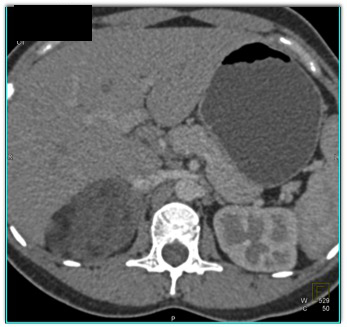

The best diagnosis in this case of an incidental adrenal mass is?

adrenal adenoma

adrenal myelolipoma

pheochromocytoma

indeterminate lesion